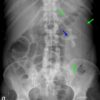

Viêm thận bể thận

» Thông tin: Nữ giới – 51 tuổi.

» Lâm sàng: Đau thắt lưng + Sốt.